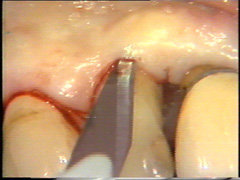

La incisión inicial se empieza alrededor de 10-15 mm distal del  último diente hasta la línea media del proceso alveolar. Esto se hace para evitar el cierre del colgajo  que está en la proximidad de la  furcación que se abre en distal del primer molar. La incisión se realiza con una presión tal para  llegar a hacer contacto con el hueso.

La incisión es entonces continuada en  bucal siguiendo la línea del margen gingival pero ubicando el corte en 1 a 1,5 mm hacia apical. La incisión debe partir de coronal del hueso alveolar en la  proximidad del diente. En el segundo premolar el bolsillo está muy profundo y aquí la incisión se ensancha para generar reducción de la bolsa  que luego es reemplazado por el colgajo.

La profundidad al sondaje en  los primeros premolares en bucal es poco profunda y aquí la incisión se ubica en el surco ginginval propiamente dicho. El escalpelo se mueve a través del tejido con un serrar suave y con pulso firme.